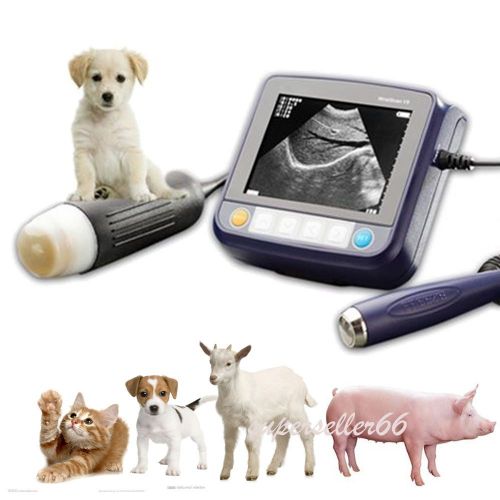

Model | 9000BV |

| CE FDA certificate | Approved | ||

| Country/Region of Manufacture | China | ||

| Warranty | 18 Months | ||

| Screen Size | 12 Inch | ||

| Probe connector | 2 | ||

| Net Weight | 6.5KG | ||

| USB Port | 1 | ||

| Machine Size | 31cm*21cm*27cm | ||

| SVGA Video Out | Yes | ||

| Image resolution | 800*600 | ||

| VGA out | Yes | ||

| Probe | Rectal probe | ||

| Other Choice | Trolley / Video Printer | ||

| Options | Linear / Convex / Micro-Convex |

Similar products from Animal Care

12" LCD Portable Digital Ultrasound Scanner 3.5Mhz Convex Probe 3D Veterinary CE

Veterinary Portable Digital Ultrasound Scanner 3.5Mhz Convex Probe External 3D

12-inch Veterinary Portable Digital Ultrasound Scanner Convex Probe External 3D

12" Veterinary Portable Digital Ultrasound Scanner Machine Convex Probe Free 3D

12" Veterinary Portable Digital Ultrasound Scanner 5.0Mhz Micro Convex Probe 3D

12-Inch Veterinary Portable Digital Ultrasound Scanner Micro-Convex External 3D

12" LCD Portable Digital Ultrasound Scanner 5.0MHz Micro-Convex 3D Veterinary CE

LCD Portable Digital Ultrasound Scanner 5.0MHz Micro-Convex Probe 3D Veterinary

12"Portable Digital Ultrasound Scanner Machine 7.5MHz Rectal Probe 3D Veterinary

12-Inch Portable Digital Ultrasound Scanner 7.5MHz Rectal Probe 3D Veterinary CE

12" LCD Portable Digital Ultrasound Scanner 7.5MHz Rectal Probe 3D Veterinary CE

Veterinary Pregnancy Mini Portable Wrist Handheld Ultrasound Scanner With Probe

Veterinary Mini Portable Handheld Wristscan Ultrasound Scanner Probe-- dog horse

Veterinary Mini Portable Handheld Wristscan Ultrasound Scanner Machine Probe CE

Veterinary WristScan Ultrasound Scanner Machine With Probe Vet Animals Pregnancy

Animals Pregnancy Wrist Scan Ultrasound Scanner Machine Probe--Pig dog cat sheep